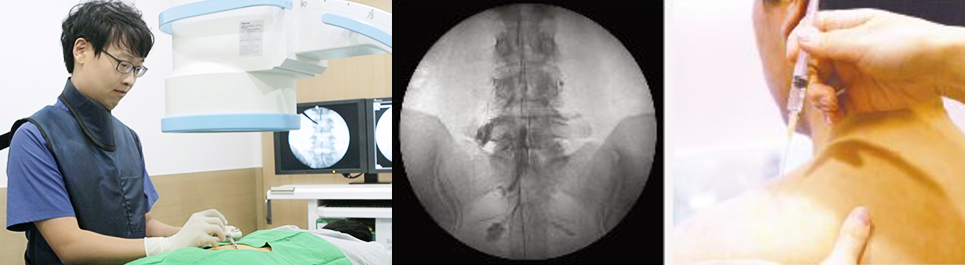

컴퓨터영상정밀주사(C-ARM)로 가는 카테터를 통해 통증 부위 안쪽으로 치료 약물을 직접 주입하는 방법입니다. 손상된 주변 조직의 염증과 부종을 감소시키고, 근육과 인대를 튼튼하게 해주는 특수 강화 시술입니다. 정상 조직들의 피해가 거의 없는 보존적 치료로 디스크 및 척추 통증 환자의 90% 이상을 치료할 수 있습니다. 또한, 이 치료법은 실시간 보이는 영상을 통해 검사와 치료가 동시에 가능합니다. 숙련된 전문의가 환자 상태를 실시간 확인하면서 시술하기 때문에 시술 시간이 길지 않고 합병증의 위험이 적은 편입니다.